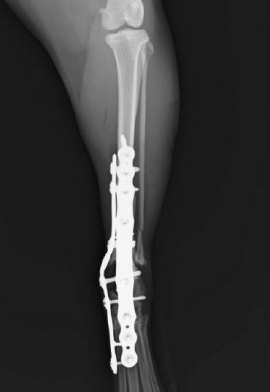

脛骨高平部水平化骨切り術 TPLO (Tibial Plateau Leveling Osteotomy)

脛骨近位を切断し、高平部を尾側かつ遠位に回転させて固定する手術方法です。

TPLOは脛骨近位を円形に骨切りし、プレートで固定する手術方法であるため、骨切りに使用する器具やインプラントのサイズによっては手術の適用に制限があります。

当院では様々なインプラントを使用しており、全てのサイズを導入しています。

小型犬から超大型犬まで治療が可能です。

術後は7日間の入院管理を行います。

入院期間中は早期回復と機能維持を目的にアイシングやリハビリを行います。

退院後は3週間自宅で運動制限を行い、安静にしてもらっています。